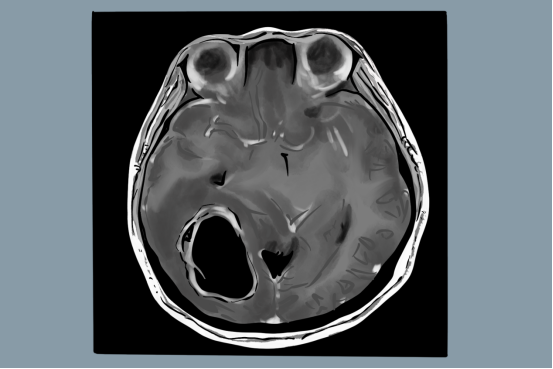

●CT或MRI检查提示有脑内占位性病变;

随着神经影像技术的进步,以DCE-MRI(磁共振动态增强)为代表的MRI影像组学,从脑胶质瘤的影像学特征、血流分布特点等多维度评价脑胶质瘤的恶性程度,为脑胶质瘤的术前分级和术后评价提供更加准确依据,也在一定程度上提高了脑胶质瘤的临床综合诊疗水平。

对于40岁以上的人群,要定期进行CT、MRI(核磁共振)、MRA(磁共振血管成像)检查,以上检查不仅可以筛查是否有脑胶质瘤,还可以排查动脉瘤以及是否有脑血管畸形。